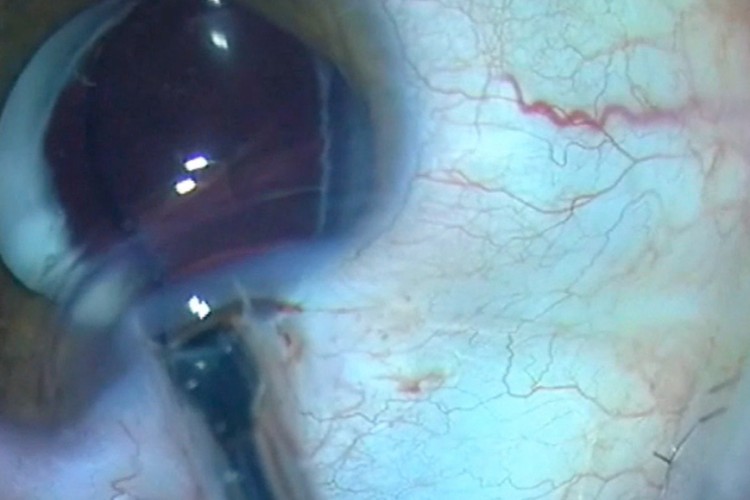

Greffe cornée Carlevale